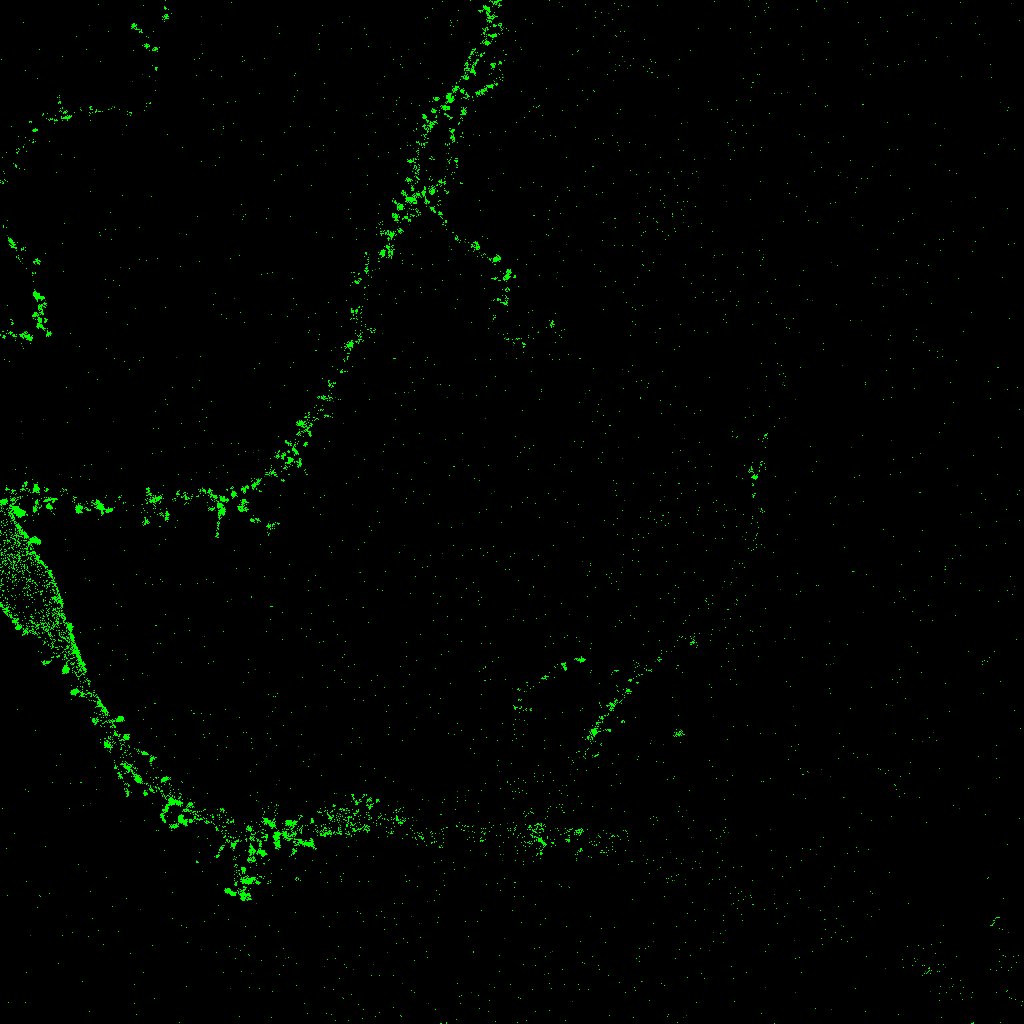

El plugin NeuronPersistentJ [14] se utiliza para detectar la estructura de una neurona a partir de una pila de imágenes en dos dimensiones (como en la figura 5). En primer lugar, se procesan las imágenes con filtros que disminuyen el ruido. En un segundo paso se aplican las ideas de homología persistente [6] y persistencia zigzag [4] explicadas en la sección 4. El resultado es una imagen 2D en la que se representa la estructura de la neurona, como muestra la figura 9.

Refer to caption

Figura 9: Resultado de NeuronPersistentJ